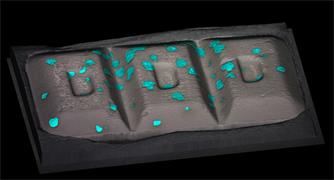

- Generate images of the formulations used in tablets, inhalers and nasal sprays at sub-micrometre spatial resolution

Rapidly generate images of your formulations with StreamLine™. This uses line focus illumination, allowing you to use higher laser powers without risk of sample damage, thereby reducing experiment times.

With the RA802 pharmaceutical analyser you can achieve imaging speeds of over 1500 spectra/s. It takes less than 2 minutes, from placing a standard tablet in the system, to generate a full, high resolution Raman image.

Ensure your chemical images are representative; use Renishaw's StreamLine. You can change resolution to suit your domain size and, because Renishaw's WiRE software can cope with massive data files, you can analyse over the entire sample surface. Powerful Renishaw features, such as Slalom (to ensure the whole surface is sampled) and HD imaging (to get crisp clear images), provide all the options you need, whatever your formulation.